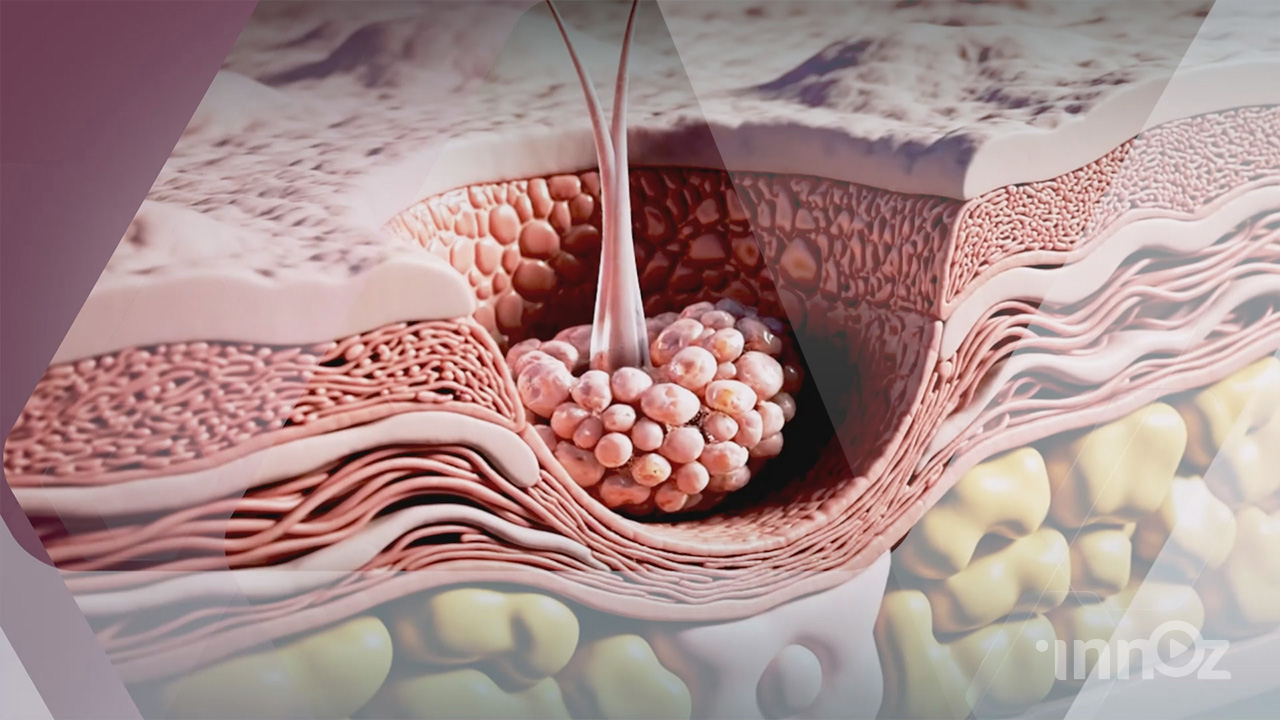

피부과